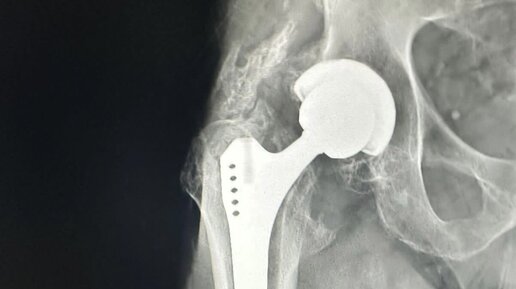

Люди старше 40 лет в той или иной степени испытывают боли в тазобедренном суставе. Зачастую причиной этому служит коксартроз(артроз тазобедренного сустава). Коксартроз обычно затрагивает людей с избыточной массой тела, ведущих малоподвижный образ жизни, и конечно людей, которые могут собрать эти причины воедино, это - люди преклонного возраста. Пациентов, которые страдают коксартрозом обычно беспокоят боли при движение в тазобедренном суставе, дискомфорт, ноющи боли по ночам, чувство что с утра нужно разработать сустав, "расходится"...